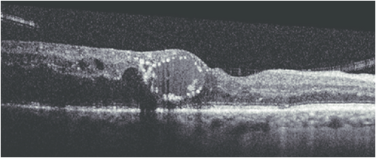

Central Serous Chorioretinopathy (CSCR)

CSCR on OCT shows neurosensory detachment along with clear subretinal fluid often associated with focal serous PED. More recently, enhanced-depth imaging SD-OCT has shown increased subfoveal choroidal thickness in some patients with CSCR, as compared to normal eyes.[25] The outer retinal dipping sign may be noted. Typically, the RPE not involved in serous PED appears straight, unlike inflammatory pathologies, including VKH disease, where the RPE may be undulated.[26]

Bacillary layer detachment (BLD)[32]

BLD is a photoreceptor-splitting detachment. Note the hyperreflective material along the outer retinal surface. A thin band at the base of cystic detachment is continuous with the adjacent ellipsoid band and the external limiting membrane.